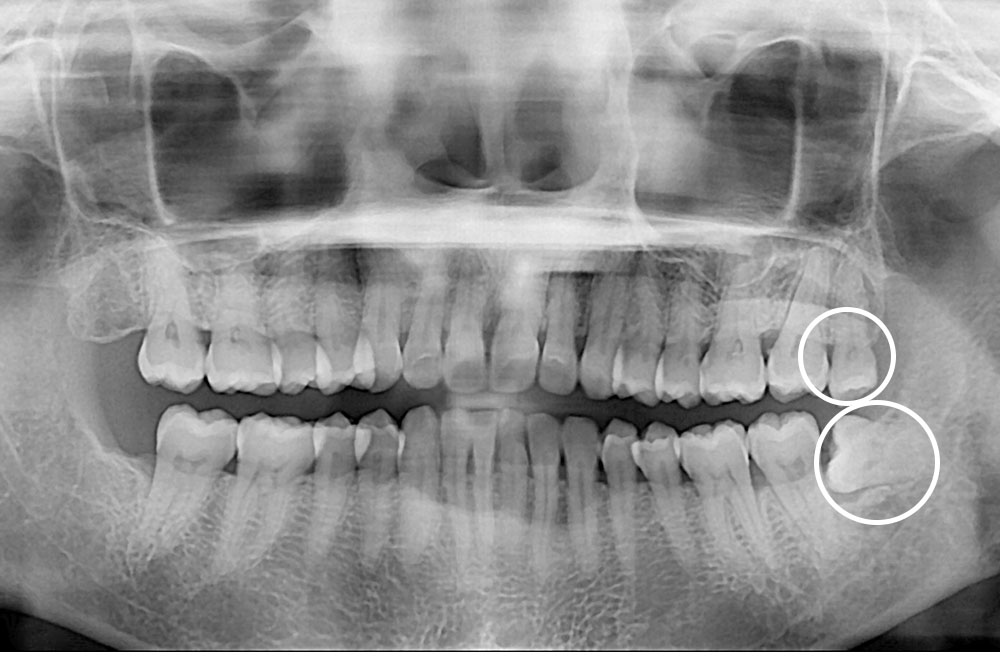

[사랑니] 매복 사랑니 발치

치료전 : 2021-07-23

치료후 : 2021-08-06

세종치과는 구강악안면외과학 박사이신 원장님이 발치하는 치과입니다.